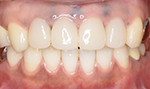

症例1

初診で前歯の保険の差し歯が変色し形も色も悪いのでセラミックで治したいと希望した患者さんです。

術後

患者さんは女性で柔らかい感じにしたいと希望がありましたので少し丸みをだして作りました。患者さんは満足しております。

術後4年経過

タバコを吸う方ですが歯の色の変色や着色また歯肉退縮もなく歯垢の付着もありませんでした。

術前

後前

4年後